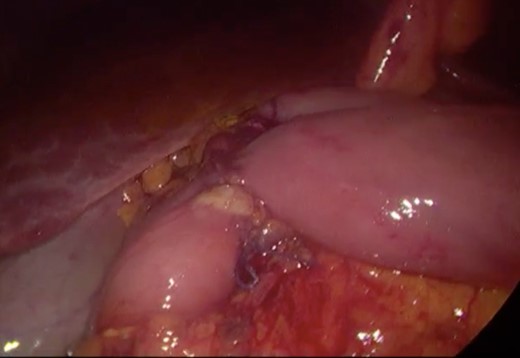

Initially, conservative management was adopted with some improvement of patient’s nutrition condition. However, as symptoms persisted, surgical treatment was recommended. Our surgical approach was a laparoscopic duodenojejunostomy with a latero-lateral stapled anastomosis between jejunum (30 cm from Treitz’s angle) and the second portion of the duodenum (Figs 5–9). The patient recovered with no pain but with a delay in diet acceptance. An upper GI contrast study was performed on the fifth post-operative day revealing a distended stomach with gastric emptying delay, but with unobstructed anastomosis, therefore without stenosis or leaks (Fig. 10). She was discharged home after 8 days with liquid diet and digestive transit restored. After 3 months of follow-up, the patient gained some weight and remained asymptomatic.

Surgery—initial laparoscopic view with distended stomach and proximal portions of duodenum.